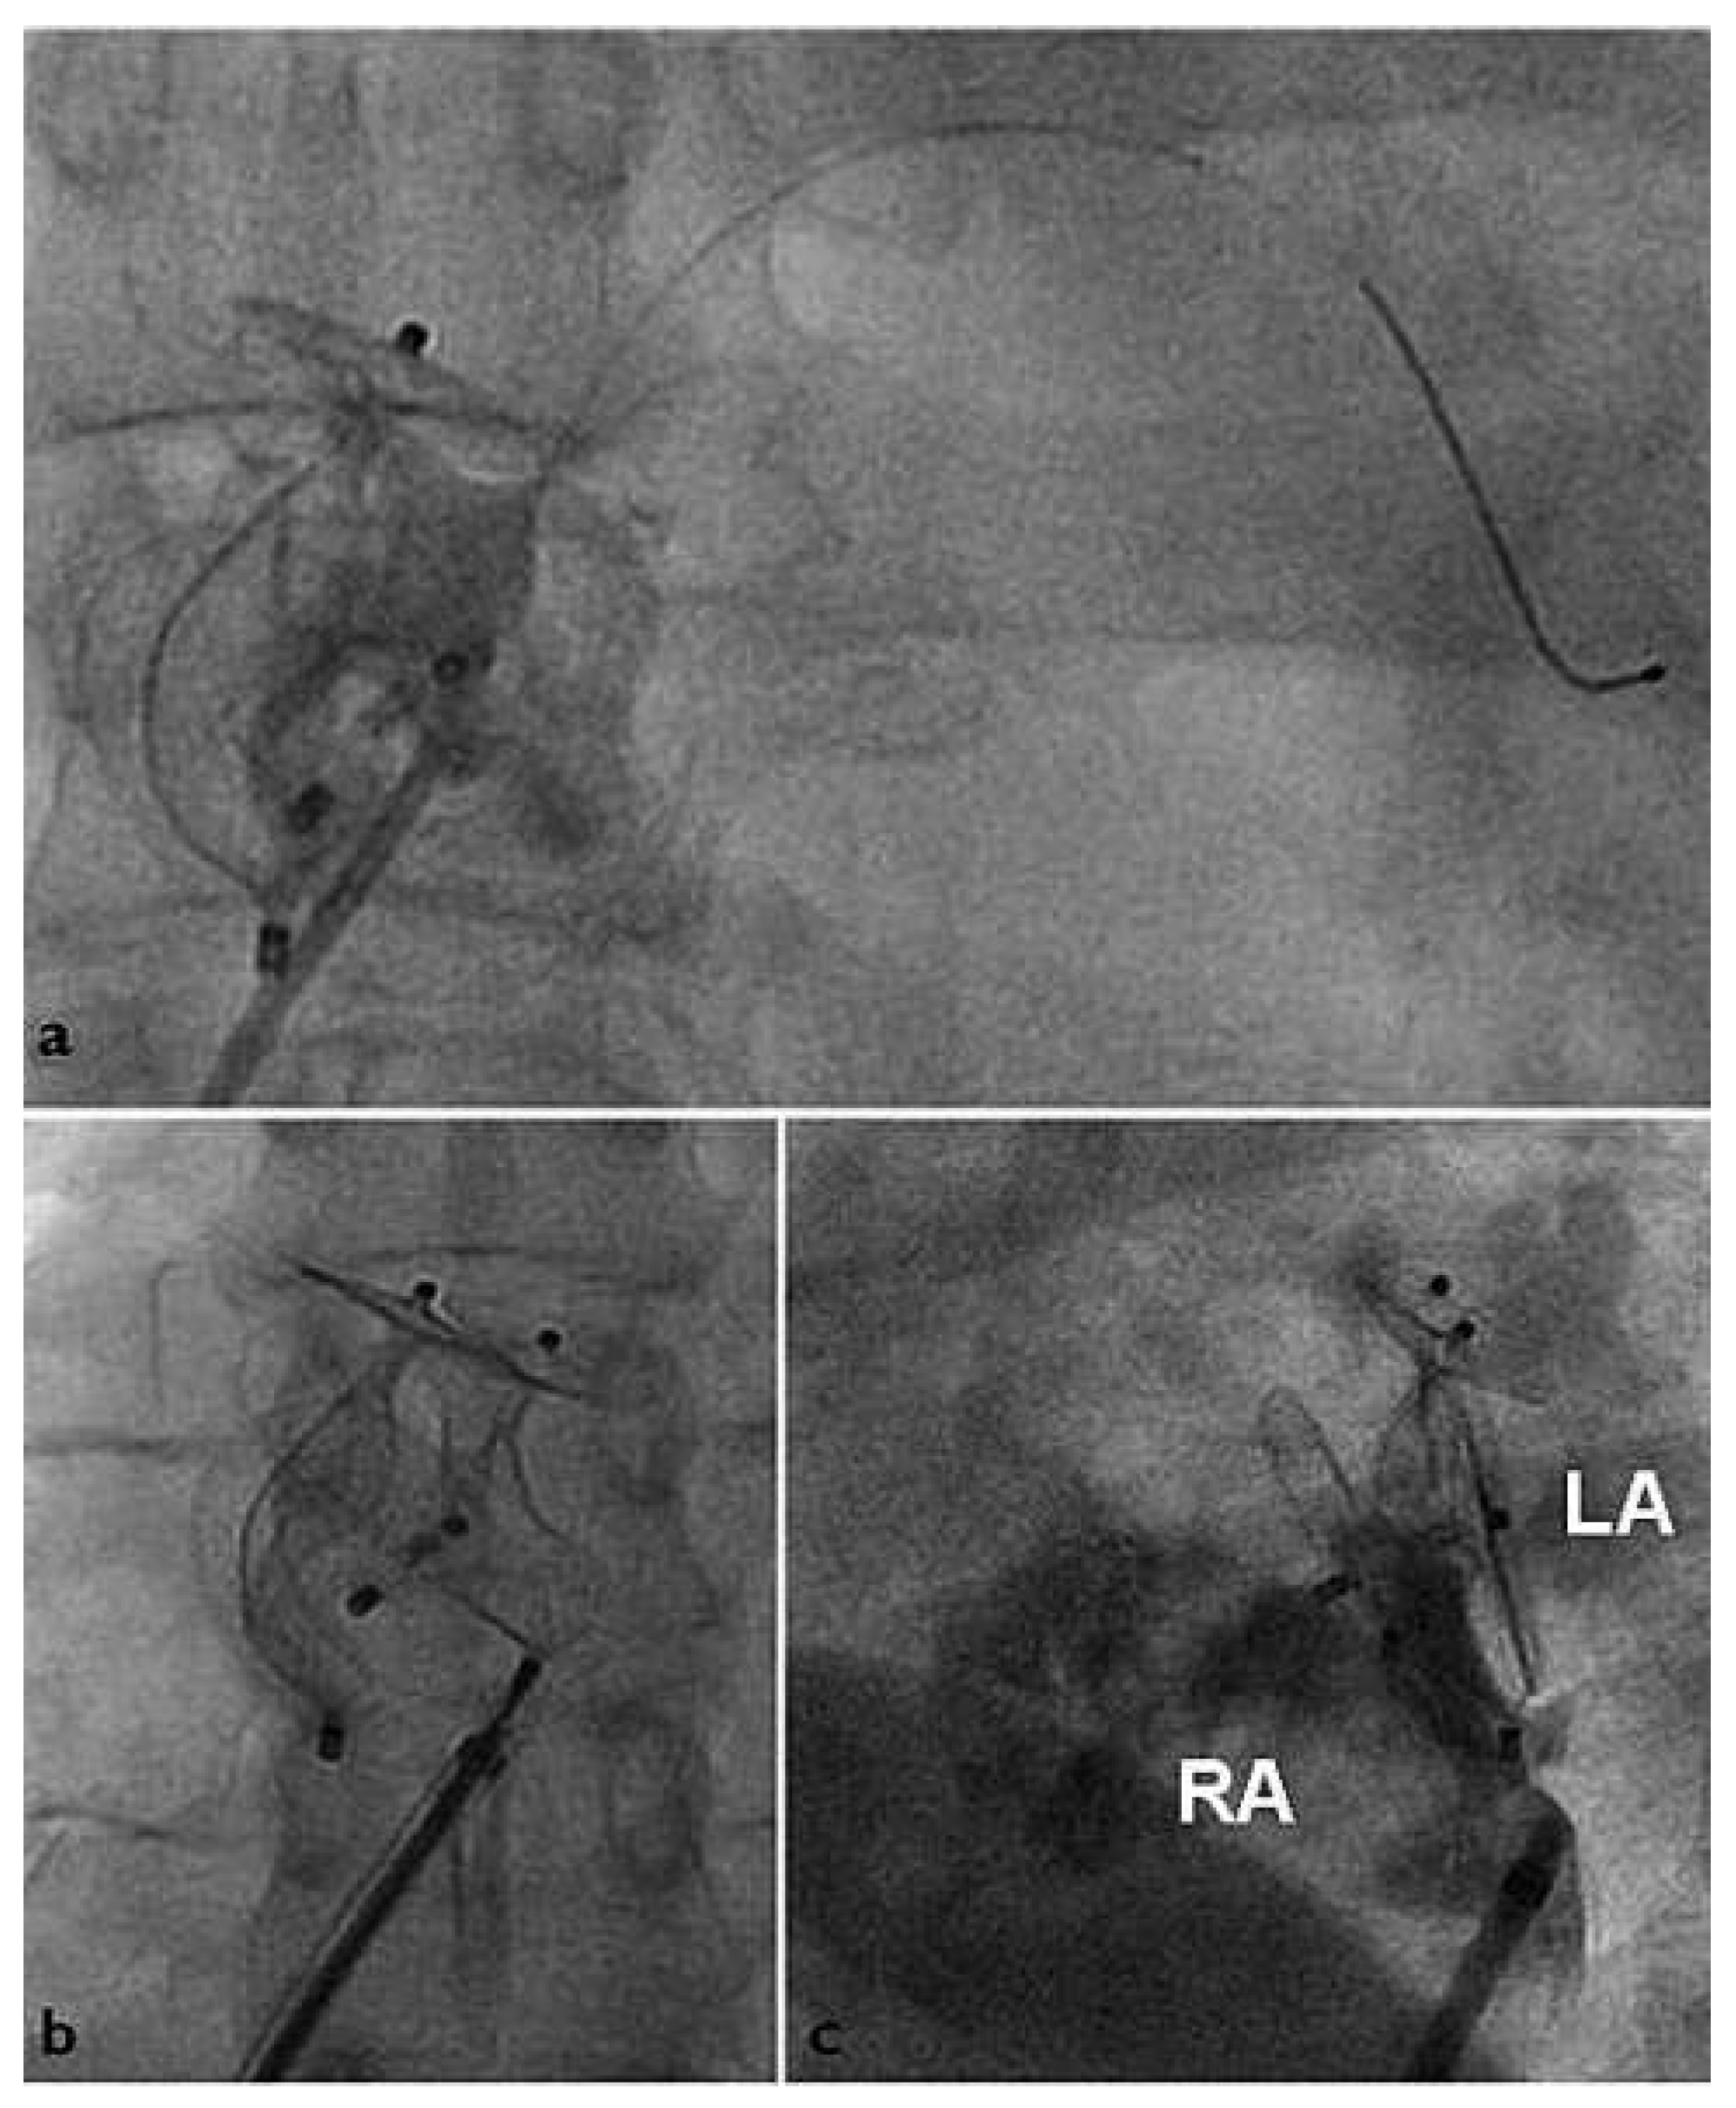

Six months after implantation of the second device, contrast TOE revealed correct position of both devices but a persisting shunt grade II (Figure 4). A third APFO (18-mm) was implanted using the same technique (Figure 5). Contrast TTE at discharge the same day assessed good position of the device without any residual shunt. Clopidogrel 75 mg was again prescribed for 1 month and acetylsalicylic acid 100 mg for 5 months. Six months after implantation of the third device, contrast TOE finally showed complete occlusion (Figure 6) and both platelet inhibitors were stopped.

Figure 5. (A) Third intervention Residual PFO passed with a 0.014 inch Magnum coronary guidewire. (B) Deployment of an 18-mm Amplatzer PFO Occluder. (C) Final angiographic result with 3 Amplatzer PFO Occluder in place. LA = left atrium; RA = right atrium.